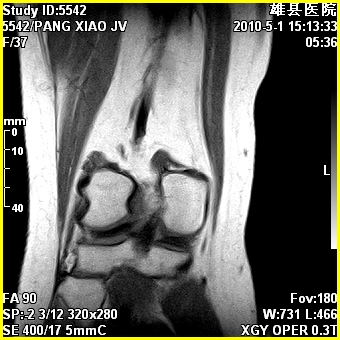

标题: MRI2894:患者右膝关节疼痛两月余,无明显外伤史 [打印本页]

标题: MRI2894:患者右膝关节疼痛两月余,无明显外伤史

右股骨下端前内侧类圆形异常信号,位于干骺端,呈长t1长t2改变,但信号不均,t1图上病灶中心见小片状稍高信号影,t2图上见散在稍低信号影,stir像呈高信号,因病灶较小,缺乏特征性改变,结合患者年龄及部位,考虑嗜酸性肉芽肿可能性大。胫骨关节面下的小囊状异常信号,如果一元论考虑则为嗜酸性肉芽肿,不过发生在这个部位的少见,二元论考虑为邻关节骨囊肿。半月板与前后交叉韧带均未见异常。

右股骨下端前内侧干骺端囊性良性病变,考虑 1内生软骨瘤 2骨囊肿 3肉芽肿。